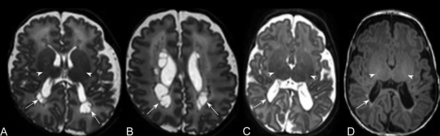

Typical MR imaging brain appearances of term-born and preterm infants, at TEA. Axial T1-(A) and T2- (B) and sagittal T1 (C)-weighted images of a term-born infant (40 weeks’ gestational age) imaged at 44 weeks PMA. Note the high-T1/low-T2 signal within the PLIC from the myelin (arrows, A and B); the complex cortical folding; small, symmetric ventricles; and the typical appearance of a normal corpus callosum (arrowheads, C). By comparison, D–F are comparable images obtained from an infant born at 25 + 2 weeks’ gestational age and imaged at 42 + 4 weeks’ PMA. This infant had no acquired focal lesions however, note the scaphocephaly, reduced cortical folding, globally thinned corpus callosum (arrowheads, F), mildly dilated ventricles, and diffuse high-T2/low-T1 signal in the white matter compared with the term infant. There is grossly normal myelination in the PLIC (arrows, D and E).

Myelin within the posterior limb of the internal capsule (PLIC) is readily identifiable in the neonatal brain; absence or marked asymmetry was considered pathological (Figs 1⇓–3).